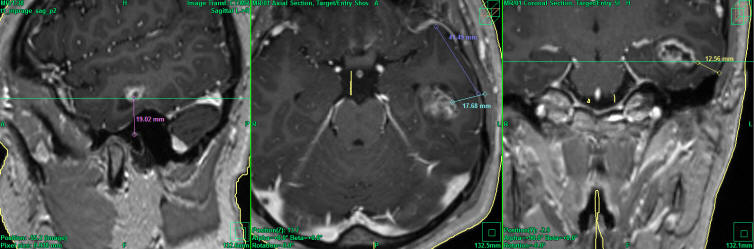

The patient was sent for new investigations and MRI of the brain performed 22-July-2015 showing the mass considerably enlarged in diameter 28.3x18.4 mm anterior to the left inferior horn. Spectroscopy showed high choline levels with glioma nature of the mass.

Localization of the tumor according to data 22-July-2015 using Inomed Planning sofware.